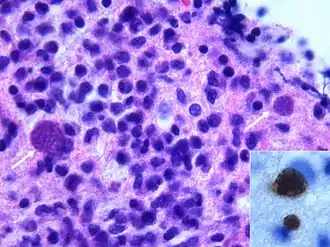

Déficit immunitaire acquis (cas du SIDA)

On décrit de rares cas où un sujet VIH+, sans immunité anti-toxoplasmique (pas de contact antérieur) contracte une toxoplasmose, mais le plus souvent il s'agit de patients immunisés contre la toxoplasmose, donc porteurs de kystes qui réactivent l'infection lors d'une baisse conséquente de leurs défenses immunitaires ; généralement, ils présentent une toxoplasmose cérébrale.

La toxoplasmose cérébrale est une maladie opportuniste dont la survenue chez les personnes séropositives marque l'évolution de l'infection par le VIH au stade de sida. Elle survient en règle générale chez des sujets séropositifs au VIH, ayant moins de 200 lymphocytes T CD4+, avec une sérologie toxoplasmique positive et ne recevant pas de prophylaxie spécifique. C'est alors que les bradyzoïtes libèrent les tachyzoïtes qui essaiment dans tout le corps via le système sanguin[37]. En 2008 en France, la toxoplasmose cérébrale représentait 12 % des personnes qui découvraient leur séropositivité au VIH après le déclenchement d'une affection opportuniste[38].